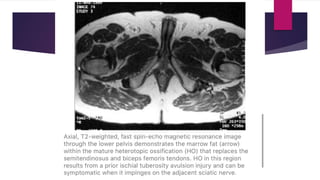

 MRI – isointense to hyperintense on T1 weighted images and

intermediate to high signal on T2 weighted images.

 MRI – overall reduced due to calcification. Important differentiating

feature could be presence of central signal intensity similar to marrow.